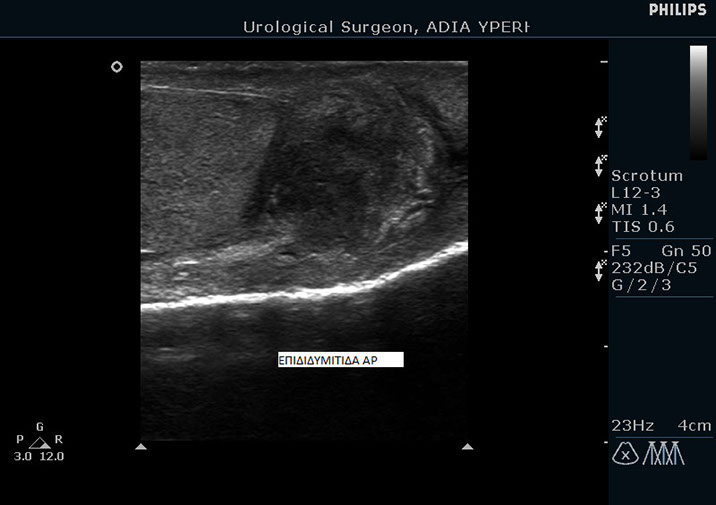

Επιδιδυμίτιδα του όρχι

Ως επιδιδυμίτιδα ορίζεται η φλεγμονή της επιδιδυμίδας σε κάποιον από τους δύο όρχεις. Επιδιδυμίτιδα ονομάζονται τα σωληνάκια που ξεκινάνε από τους όρχεις και μεταφέρουν το σπέρμα στην οπίσθια ουρήθρα.

Η διάγνωση γίνεται εύκολα από τον ουρολόγο με τη βοήθεια υπερήχων και της κλινικής εξέτασης.